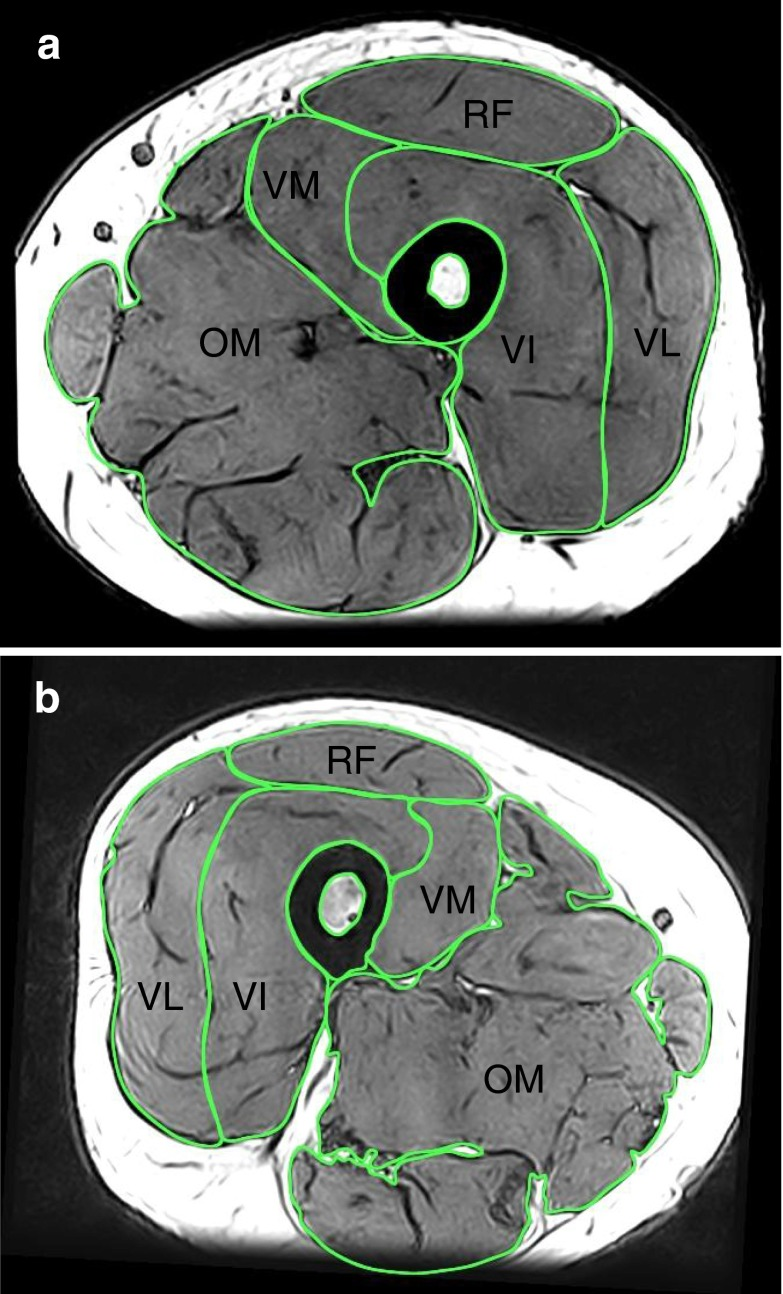

其中,大腿肌肉是「重灾区」:MRI 影像显示,70 岁时的大腿肌肉体积比 20 多岁时少了近四分之一[7]。

图示:a图为 22 岁男性;b图为 76 岁男性,股骨截面处可见大腿肌肉横截面积明显减少。

图源:Thigh muscle volume in relation to age, sex and femur volume - PMC